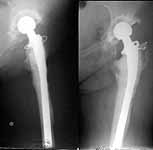

A female (birthdate 1948) was operated in 1995 because of the hip arthritis - THA (Phoenix). 1997 - revision THA with a cement Beznoska (the images attached). Recent weeks she marked pain in the femur and instability - xrays revealed stem migration and shaft fracture.

If a revision implant with super-long stem is not available, what plan is optimal? At the moment they plan to remove implant, cement, perform bone grafting of the proximal femoral end and nailing, and after healing of the shaft - nail removal and conventional revision THA.